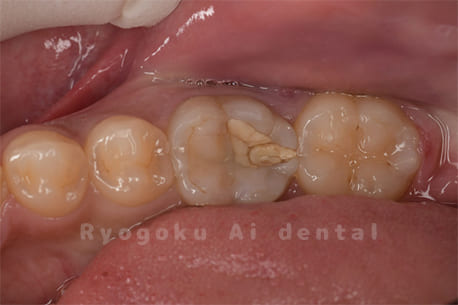

Case27

歯牙移植術後咬合面

-

歯牙移植術前側面

歯牙移植術中側面

歯牙移植術後側面

部分矯正術前咬合面

部分矯正術中咬合面

部分矯正術後咬合面

部分矯正術前側面

部分矯正術中側面

部分矯正術後側面

- 原因

- 重度カリエス

- 治療内容

- 自家歯牙移植、部分矯正

- 治療費用

- 220,000円(移植費用)

110,000円(部分矯正費用)

虫歯が大きく、保存不可能となった歯を上の親知らずと交換する自家歯牙移植を行いました。移植歯が小ぶりであったため、部分矯正を行い問題なく噛み合い、経過良好です。